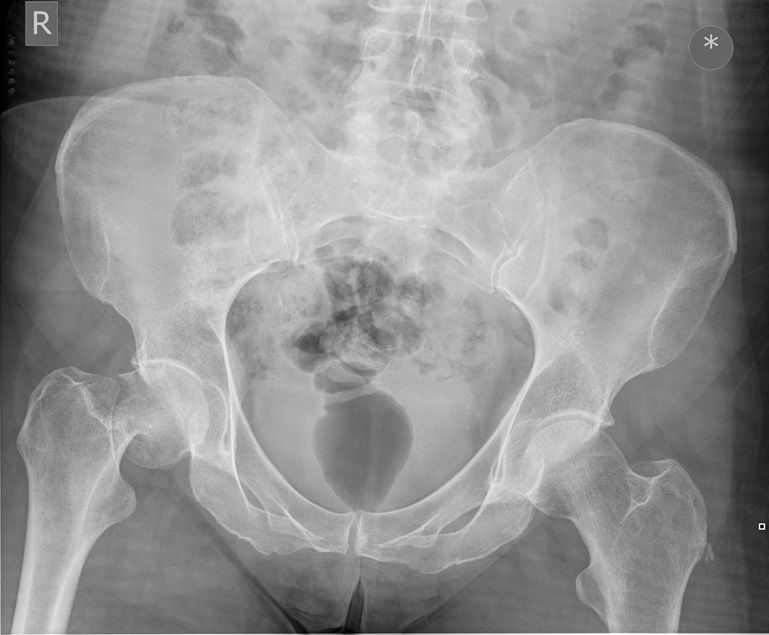

Question 1

Question

Which operation would you chose?

Answer

• THR

• Hemiarthroplasty